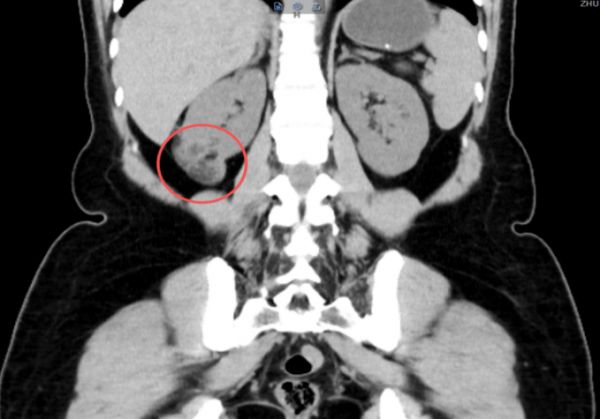

术前CT检查

李女士入院后常规完善检查,术前评估右侧肾错构瘤具备保肾条件,左侧肾错构瘤尚小,可以先定期随访观察。由泌尿外科专家褚靖副院长、郑明康主任团队为李女士行腹腔镜下右肾错构切除术(保肾手术),手术非常成功。术后李女士如期康复出院。近期复查超声提示右肾大小正常、肾实质均匀,恢复良好。